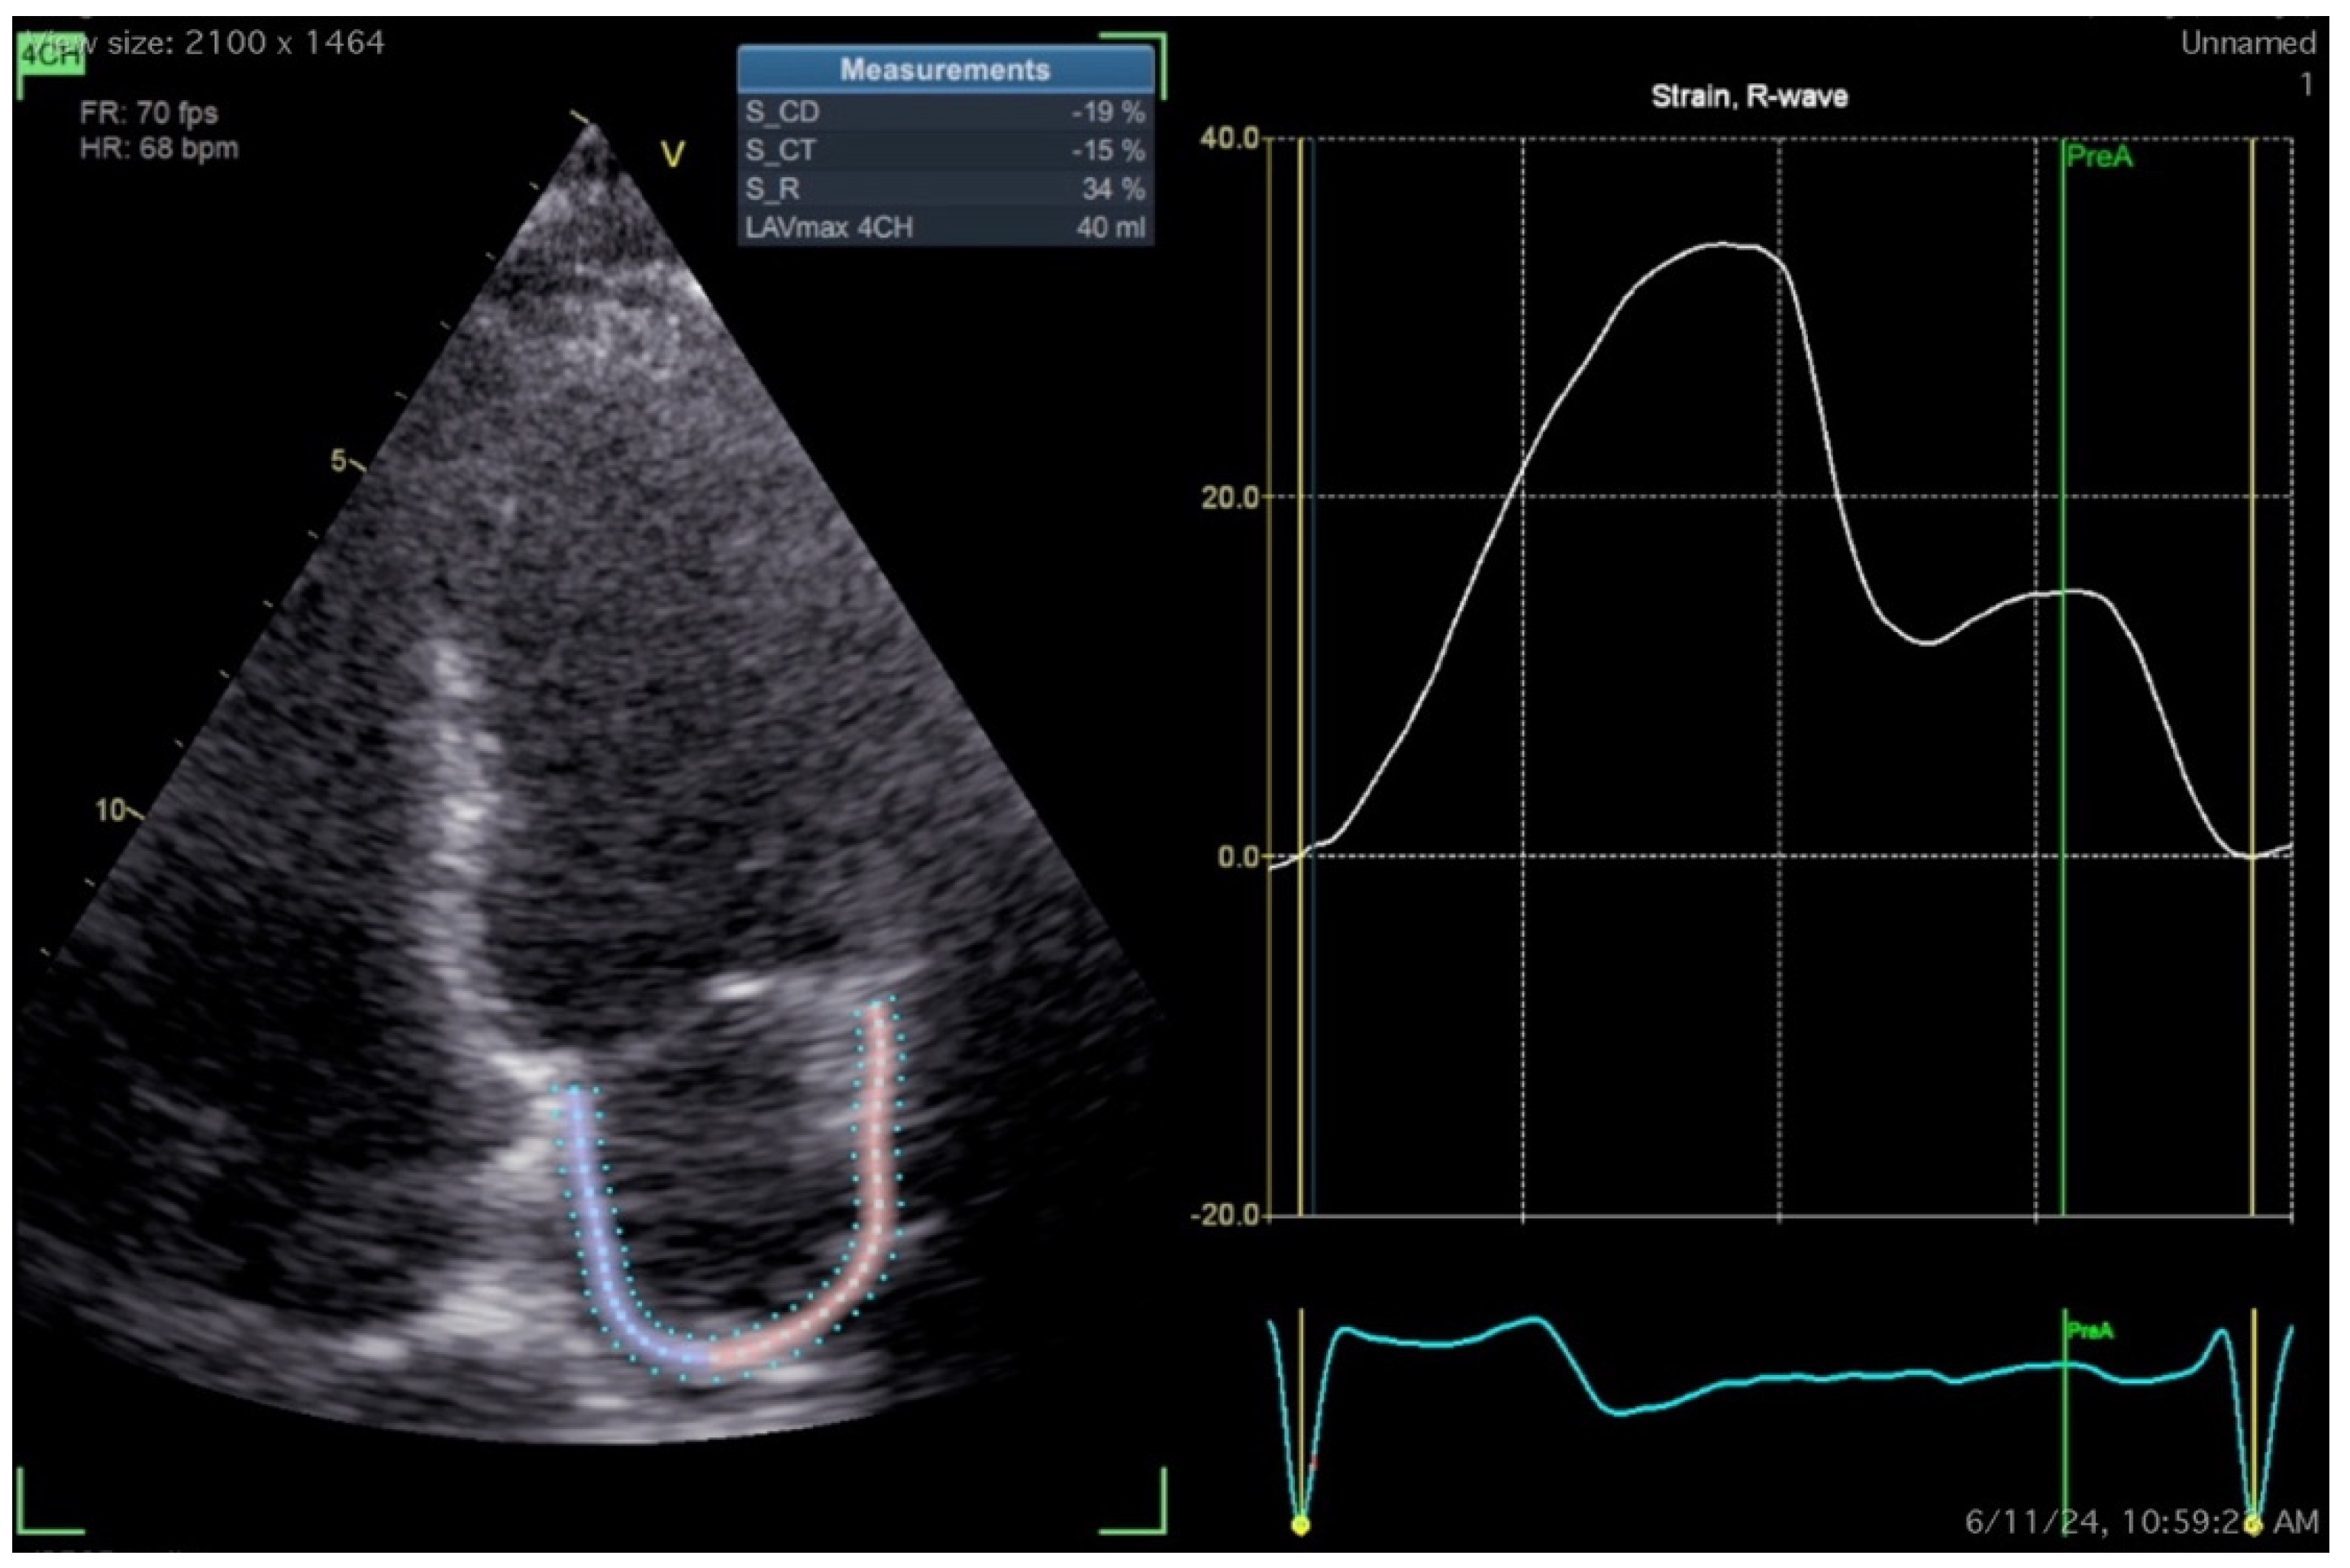

| Echocardiographic parameter | Recurrence | No Recurrence |

|---|---|---|

| LA diameter (LAD) [97] | Variable, >40mm is enlarged | |

| LA volume (LAV)/LA volume index (LAVi) [98] | Variable, most agree >153ml/>34ml/m2 favours recurrence | |

| LA sphericity index [101] | >0.678 | ≤0.678 |

| LA reservoir strain (LASr) [135] | 39% (95% CI, 38%–41%) | |

| LA conduit strain (LAScd)* [135] | 23% (95% CI, 21%–25%) | |

| LA contraction strain (LASct)* [135] | 17% (95% CI, 16%–19%) | |

| Total atrial conduction time (PA-TDI)* [110] | 146.7±20.4 ms | 130.1 ±23.0 ms |

| LA mechanical dispersion (LA-MD) [116] | 38 ± 14 ms | 30 ± 12 ms |

| E/A [121] | 1.8 ± 0.9 | 1.5 ± 0.9 |

| DT [121] | 214 ± 67 ms | 243 ± 68 ms |

| E/E’ [118] | >14 | ≤14 |

| L-wave [120] | Presence | - |

| Left atrioventricular coupling index (LACI) [122] | 44.0 (43.0–45.0)% | 49.5 (47.0–53.0) % |

| LA stiffness index (LASi) [123,124] | 0.83±0.46 or 1.64 ± 1.70 | 0.40±0.22 or 0.61 ± 0.46 |

| Mitral/tricuspid regurgitation (MR/ TR) [128] | More than mild | - |

| Pulmonary artery pressure (PAP) [129] | ≥35 mmHg | < 35mmHg |

| TAPSE/PAP [130] | ≤ 0.57 | >0.57 |

| Right atrial volume (RAV) [132] | ≥87 ml | |